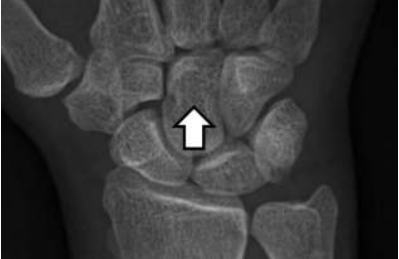

A imagem apresenta uma radiografia do punho, com destaque para os ossos do carpo, observe:

Considerando a disposição anatômica correta dos ossos carpais, o osso em destaque corresponde ao: